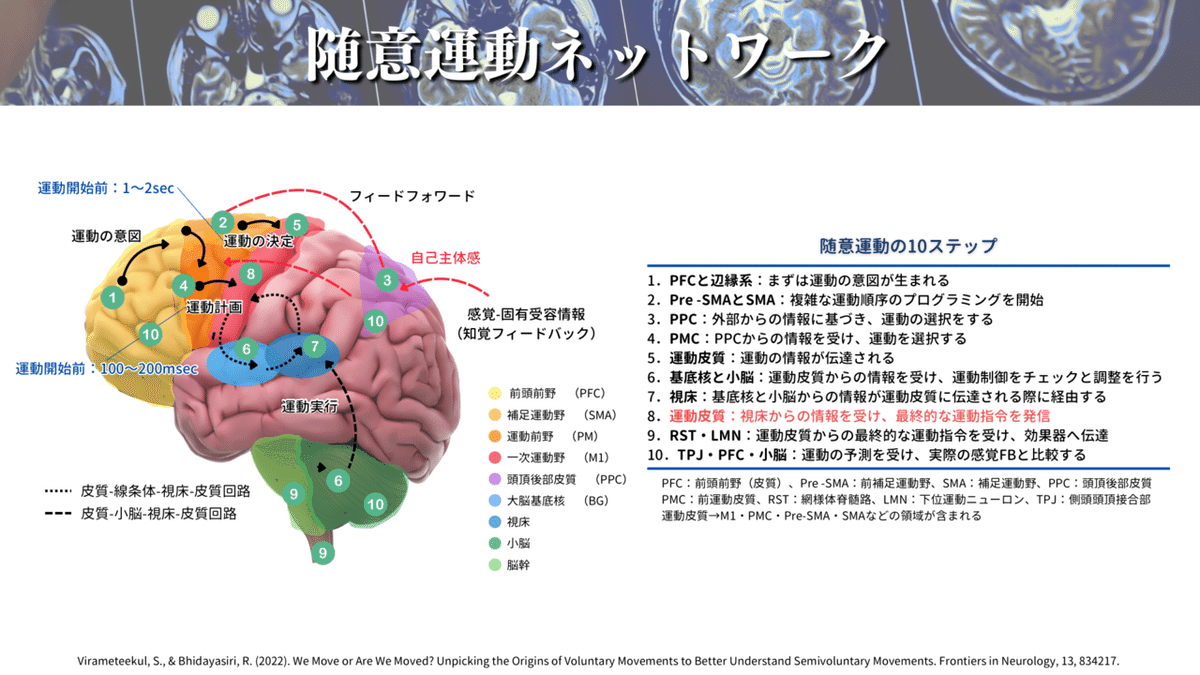

そもそも M1・CSTがどのような時に活動するのかと言いますと、随意運動をする時です🏃♀️

人間は、何かしたいと思った時に運動を実行するわけですが、この運動を実行するときに手足や口を動かしているのがM1・CSTです☝️

話を戻しまして、M1について簡単に解説します🧠

M1にはホムンクルスと呼ばれる身体機能局在があります(下図)!

簡単にいうと手を動かすことに特化した領域や、足を動かすことに特化した領域があるということです🖐️🦶(ちなみにこれを効果器特異的領域と言います)

最近では、運動実行だけなく、運動の計画にも関与する領域があるということも分かってきましたが、ここで話すと長くなりますので、⬇️の記事に詳細は譲りますね🙇♂️